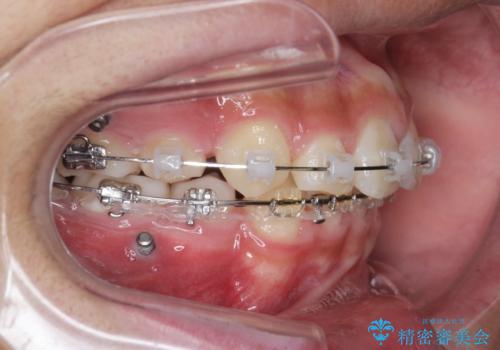

- 前歯のがたつきが原因で歯ブラシしづらい、見た目を改善したい!と矯正治療を希望され来院されました。

スペースの不足が見られるため、小臼歯の4本抜歯を行いマルチブラケットを用いた矯正治療を計画します。

噛み締めが強く、治療に時間がかかりましたが矯正治療の仕上がりに満足いただくことができました。